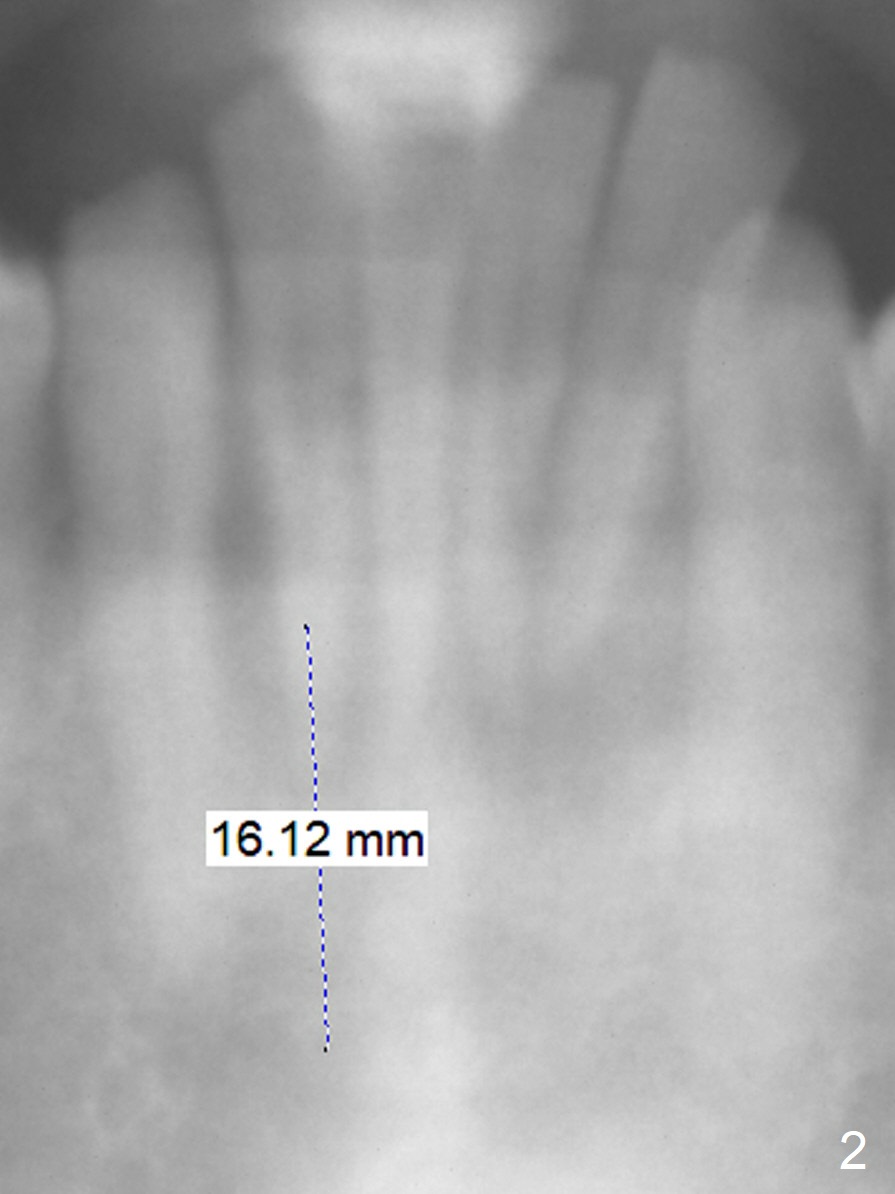

A 36-year-old man has generalized periodontitis (Fig.1). The mobile lower incisors will be extracted for immediate provisional FPD (Fig.2). The initial depth will be 16 mm. Get ready 2 of 1.2 mm drill. If the affected teeth are well aligned, take Alginate impression for surgical stent. In fact the patient has taken CT, which shows narrow 2-piece implants appropriate for the sites.